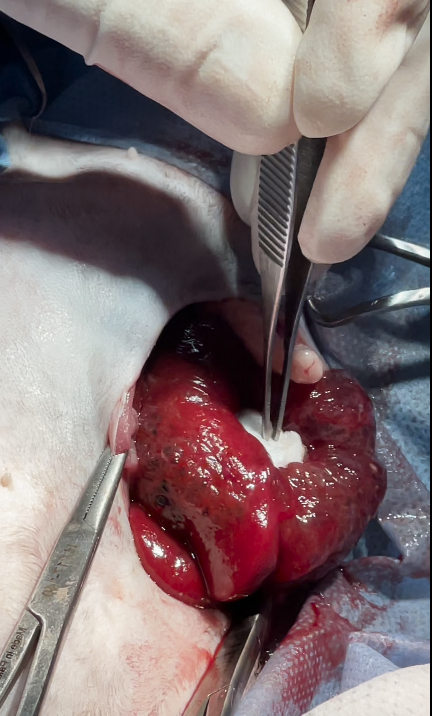

Surgical excision or partial hepatectomy is the treatment of choice.

in this case only biopsy sampling was obtained due to these reasons

owner was informed intraoperatively with :

lesion was close to major hepatic vessels & bile ducts, the risk of intraoperative bleeding or biliary leakage would be high, discouraging full lobectomy.

non-invasive, benign nature: conservative management was chosen instead of aggressive surgery

The cat’s advanced age (14 years) and possible comorbidities increased anesthesia and surgical risks

owners declined extensive surgery for risk reasons, opting for palliative management